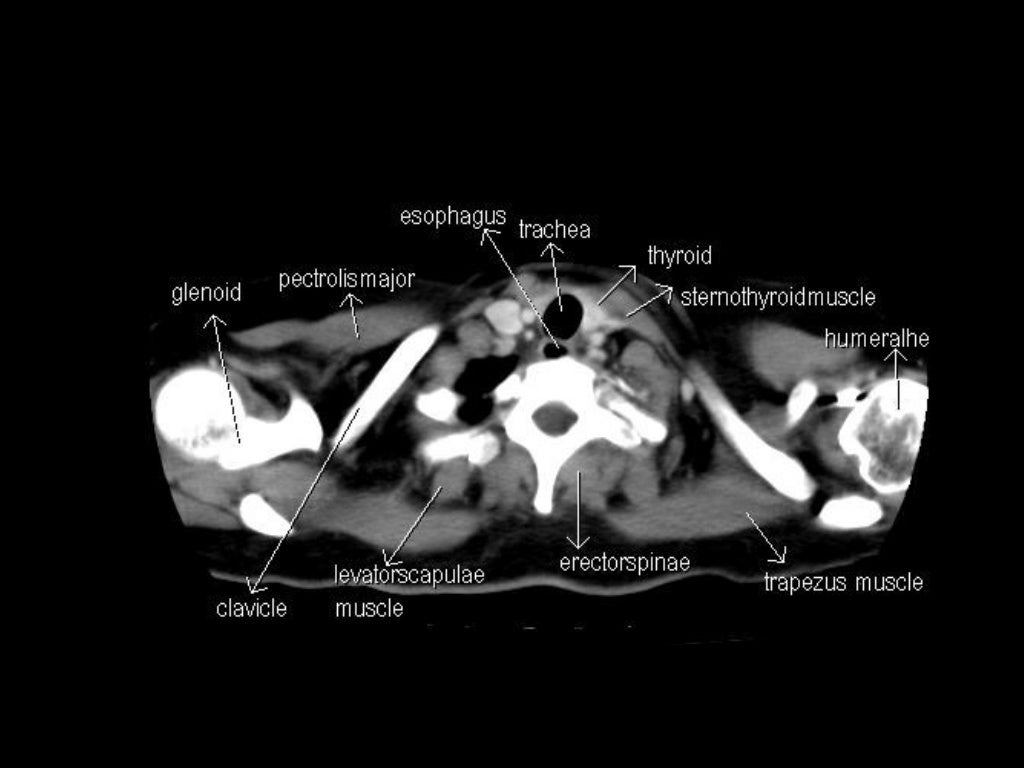

Ct Anatomy Study . It is performed with a higher radiation dose and larger dose of iv contrast, which helps to evaluate subtle areas of bowel inflammation. To get the full picture of abdominal anatomy, the examiner needs to move through the slices from cranial (proximal) to caudal (distal) while examining structures from their beginning. Radiological anatomy is where your human anatomy knowledge meets clinical practice. This case is used in 82. Explore detailed anatomical views and multiple modalities (over 8,900 anatomic structures and more than 870,000 translated. But instead of creating a flat, 2d image, a ct. What is a ct scan? Computed tomography (ct) scans are an extremely common imaging modality. A ct (computed tomography) scan is a type of imaging test. In this article, we will outline the basic principles. Annotated teaching ct head in standard and bone windows. This article lists a series of labeled imaging anatomy cases by body region and modality. Normal ct head with annotated and original images.

In this article, we will outline the basic principles. Radiological anatomy is where your human anatomy knowledge meets clinical practice. This case is used in 82. This article lists a series of labeled imaging anatomy cases by body region and modality. Annotated teaching ct head in standard and bone windows. Explore detailed anatomical views and multiple modalities (over 8,900 anatomic structures and more than 870,000 translated. Normal ct head with annotated and original images. A ct (computed tomography) scan is a type of imaging test. Computed tomography (ct) scans are an extremely common imaging modality. It is performed with a higher radiation dose and larger dose of iv contrast, which helps to evaluate subtle areas of bowel inflammation.